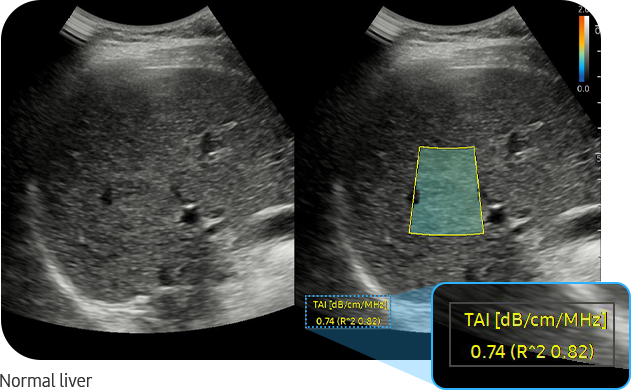

TAI™ (Tissue Attenuation Imaging) is a tool that quantitatively measures the attenuation of ultrasound signals received from the liver. TAI™ quantifies attenuation based on changes in the center frequency under the optimal transmission and reception conditions.